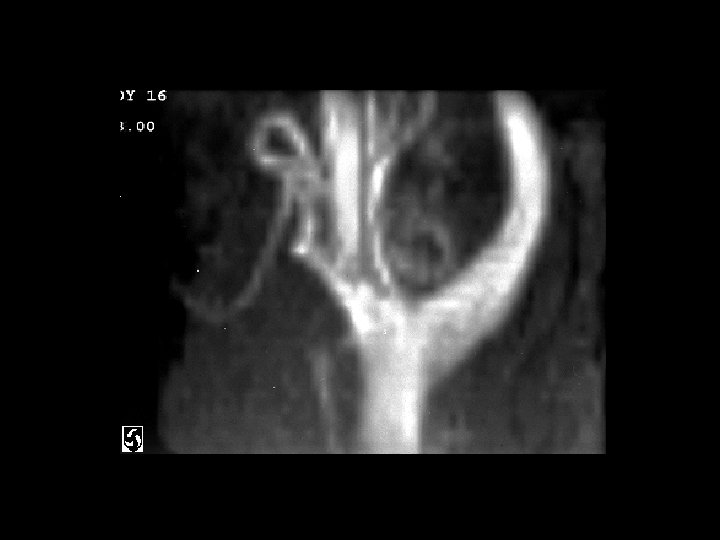

Carotid body paraganglioma • • Findings: – Intensely enhancing mass in the carotid sheath that splays the internal and external carotid arteries ddx: – Glomus vagali – Carotid aneurysm